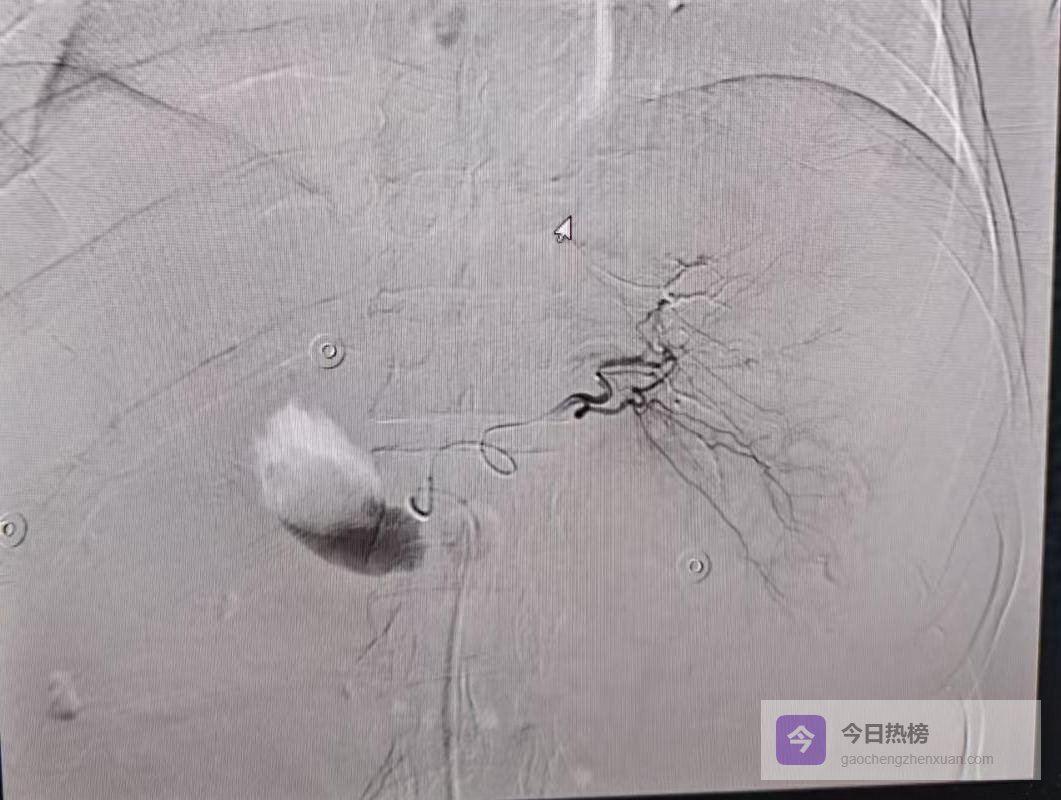

TAE被誉为“止血黄金术”:股动脉穿刺一个小针眼,导管顺着血管网直达出血点,用微球或弹簧圈把血管“堵死”,既快又准,还能保住大部分肝功能。

第2步:导管超选至肝动脉,前两次因血管变异未到位,团队冷静第三次尝试;

第3步:精准注入栓塞材料,出血立即停止。

再次造影显示,原来喷涌的血管已安静如初。术后患者被送入ICU,次日血压平稳,三天后转回普通病房,一周后顺利出院。